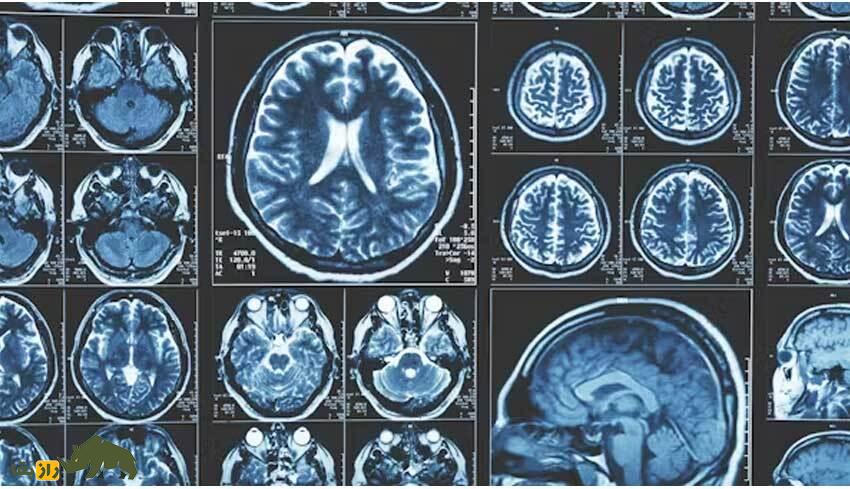

به گزارش راز بقا، چگونگی پردازش اطلاعات در مغز انسان برای رسیدن به این دستاوردها، سوالی است که جذابیت بیپایانی دارد، اما در عین حال هیچ پاسخ قطعی برایش نیست.

درک ما از عملکرد مغز در طول سالها تغییر کرده است. مدلهای نظری فعلی مغز را به عنوان یک «سیستم پردازش اطلاعات توزیع شده» توصیف میکنند. این یعنی مغز دارای اجزای متمایزی است که به طور محکم از طریق سیمکشی مغز به هم متصل شدهاند. برای تعامل با یکدیگر، مناطق از طریق سیستم سیگنالهای ورودی و خروجی مبادله اطلاعات میکنند.

با اینحال، این تنها بخش کوچکی از یک تصویر پیچیدهتر است. در مطالعهای که در “Nature Neuroscience” منتشر شد، با استفاده از شواهدی از گونههای مختلف و چندین رشته علوم اعصاب، نشان داده شد که فقط یک نوع پردازش اطلاعات در مغز وجود ندارد. نحوه پردازش اطلاعات نیز بین انسان و سایر نخستیها متفاوت است، که ممکن است توضیح دهد که چرا تواناییهای شناختی گونه ما بسیار برتر است.

برای پی بردن به این موضوع، به دادههای تصویربرداری مغز و تجزیه و تحلیل ژنتیکی گونههای مختلف نگاه کردیم. ما دریافتیم که فعل و انفعالات همافزایی، نسبت بیشتری از کل جریان اطلاعات در مغز انسان را نسبت به مغز میمونهای ماکاک تشکیل میدهند. در مقابل، مغز هر دو گونه از نظر میزان تکیه بر اطلاعات اضافی برابر است.